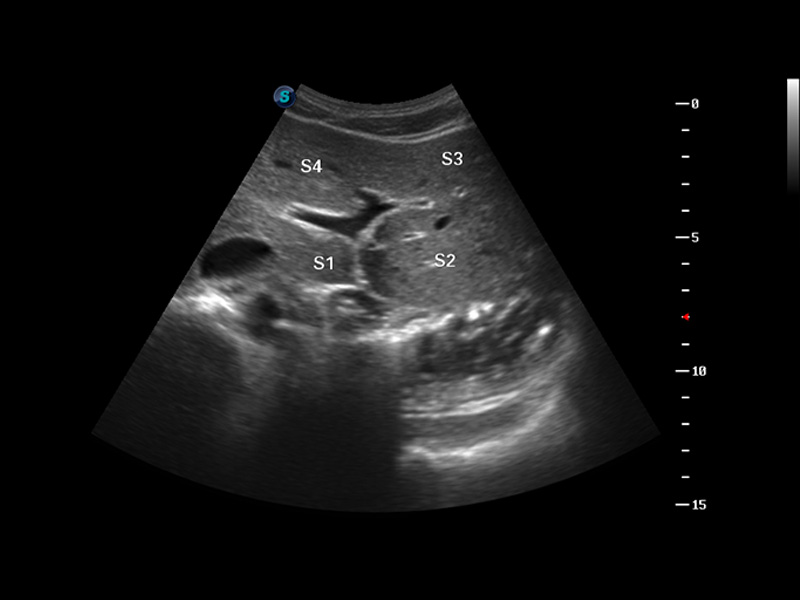

S8 EXP便携式彩色多普勒超声诊断仪是美狮贵宾会官网研发的高端全身应用型便携彩超。高通道的VIS平台融合可视化(Visual)、智能化(Intelligent)和人性化(Smart)的特点,配以美狮贵宾会官网自主研发生产的探头大家族,使您能够快速、准确的获得病人信息,提高工作效率的同时减轻疲劳。

3D/4D成像